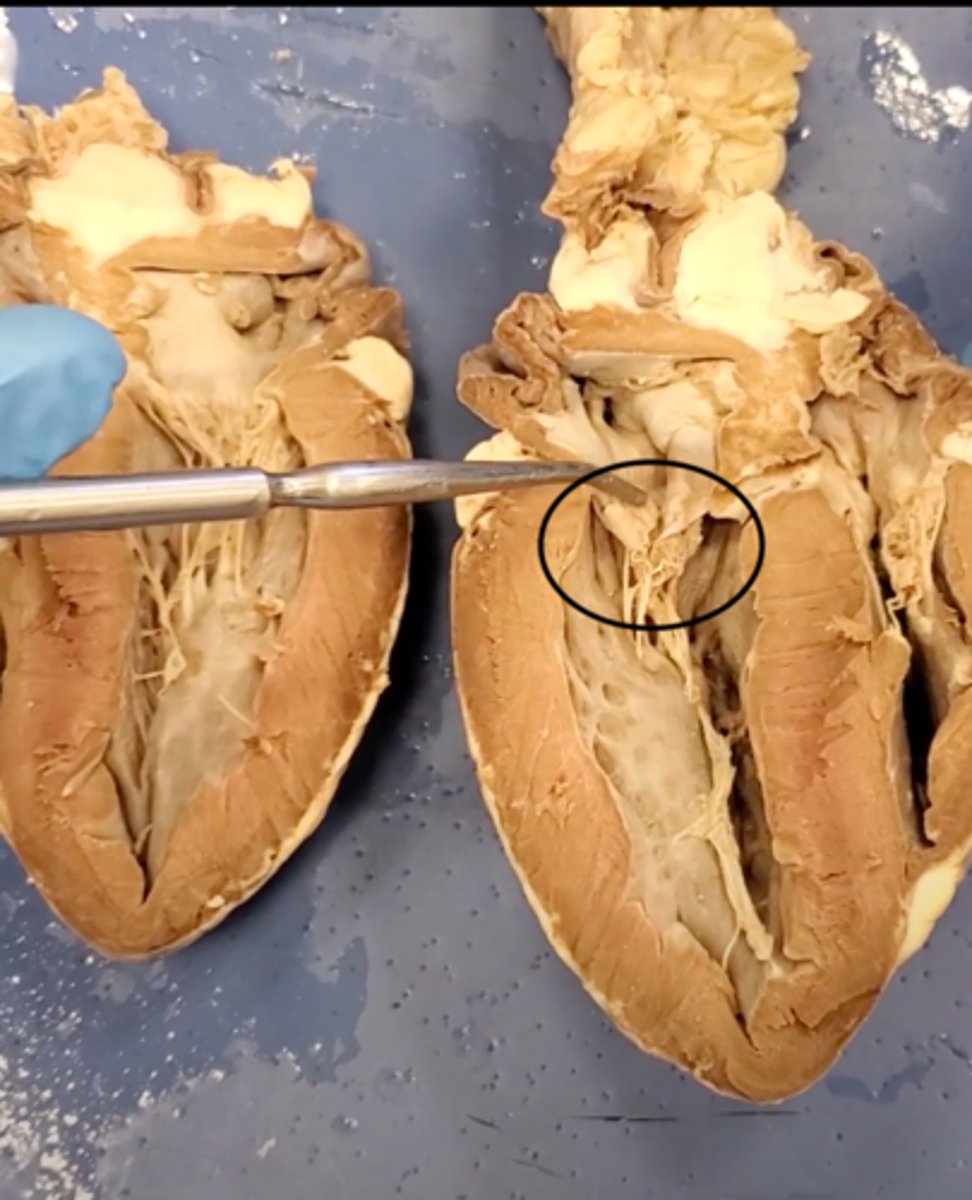

Tricuspid Valve (Right Atrioventricular Valve)

1-valve

Bicuspid valve (Left Atrioventricular Valve)

2-valve

Pulmonary Semilunar Valve

3-valve

Aortic Semilunar Valve

4-valve

Right Atrium

1-chamber

Left Atrium

2-chamber

Right Ventricle

3-chamber

Left Ventricle

4-chamber

Inferior Vena Cava

5-A vein that is the largest vein in the human body and returns blood to the right atrium of the heart from bodily parts below the diaphragm.

Superior Vena Cava

6-A vein that is the second largest vein in the human body and returns blood to the right atrium of the heart from the upper half of the body.

Aorta

7-The large arterial trunk that carries blood from the heart to be distributed by branch arteries through the body.

Pulmonary Trunk

8-carries blood from right ventricle to pulmonary arteries

Pulmonary veins

9-a vein carrying oxygenated blood from the lungs to the left atrium of the heart.

yellow sash of fat that tells you this if the front side of the heart (dissection)

pulmonary trunk (dissection)

t-shaped ribbon of fat on back side of heart (dissection)

left auricle (dissection)

right auricle (dissection)

left ventricle (dissection)

right ventricle (dissection)

right atrium (dissection)

left atrium (dissection)

bicuspid valve (dissection)

tricuspid valve (dissection)

aortic semilunar valve (dissection)

located between the left ventricle and the aorta

chordae tendineae (dissection)

thin bands of fibrous tissue that attach to the valves in the heart and prevent them from inverting